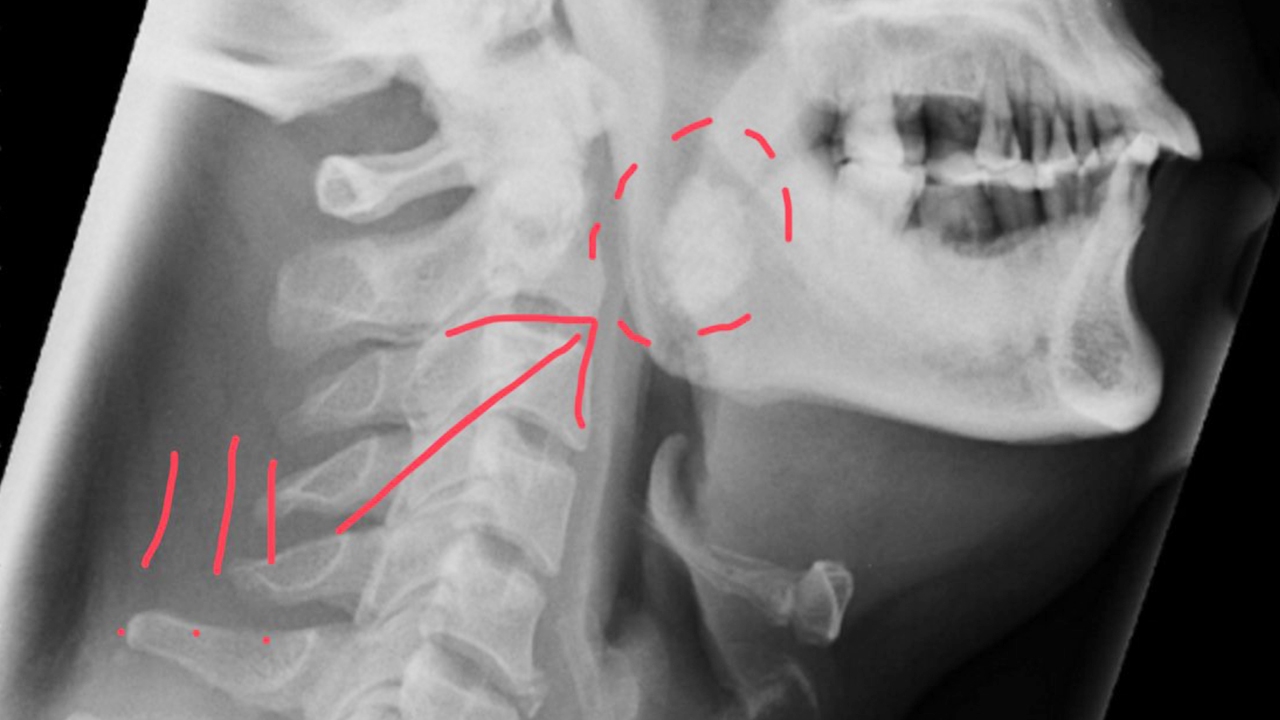

โดยผลเอกซเรย์พบว่า บริเวณดังกล่าวมีก้อนขาวๆ ประกอบกับคนไข้มีประวัติสูบบุหรี่และเคี้ยวหมาก ซึ่งเป็นปัจจัยเสี่ยงของมะเร็งช่องปากและลำคอ เมื่อผ่าออกมาจึงพบว่า ไม่ใช่มะเร็ง แต่มันคือ นิ่วทอนซิล ขนาดใหญ่กว่า 2 เซนติเมตร